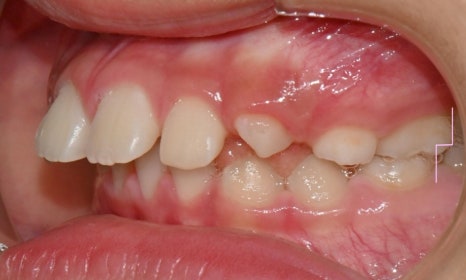

본 환자는 앞니가 점점 돌출된다는 주소로 치과에 내원하였으며, 앞니가 많이 뻗쳐있었고 과개교합 양상도 보였습니다. 또한 어금니 위치 관계도 2급(아래 어금니가 뒤로 후퇴하여 물리는 위치 관계) 이었습니다.

2024.8.3. 초진

편안하게 입술을 다물었을 때 후퇴된 아래턱 및 돌출된 위 앞니가 하순에 닿아 눌러서 아래턱은 후퇴되어 있음에도 아래 입술은 오히려 돌출감이 있었습니다.

약 9개월간 2급 액티베이터와 헤드기어 착용 후 모습입니다.

2025.5.16.

어금니 관계의 위치변화